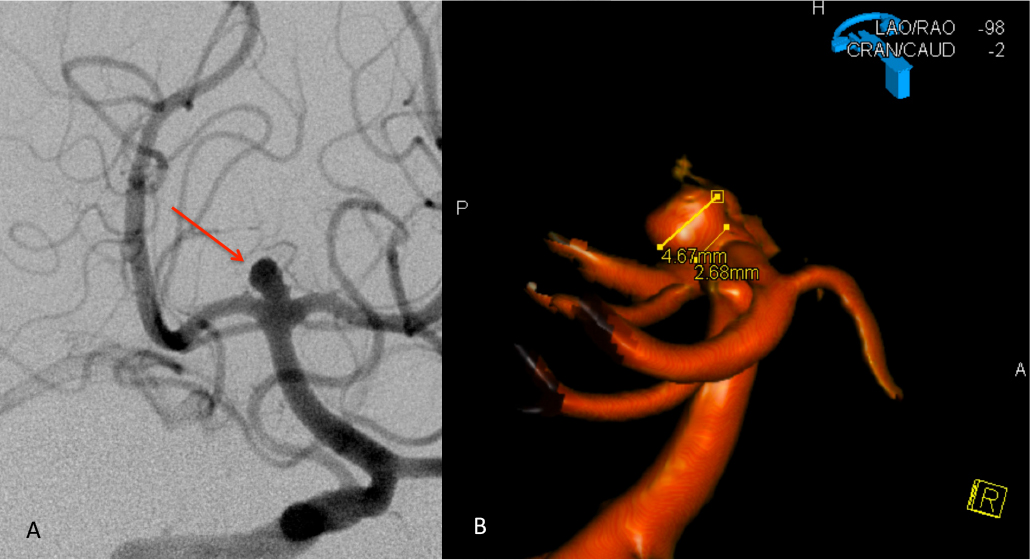

Urgent Cerebral Angiography confirmed a 5 mm posteriorly projecting aneurysm of the Basilar Artery Apex (Figure 2 A, B). Based on the location, morphology, and posterior projection, we decided to proceed to coil embolization of this high-risk aneurysm to prevent catastrophic re-bleeding and afford us the opportunity to maximize critical care for this patient during his hospital course. In this aneurysm, the dome-neck ratio was favorable from primary coiling, which was successfully performed resulting in near-complete embolization of the aneurysm (Figure 3 A, B). After 2 weeks of continued critical current l, endovascular, and neurosurgical care for complications of subarachnoid hemorrhage, including vasospasm and hydrocephalous, he was able to make a complete recovery and ultimately discharged home to complete his recovery, having regained all neurologic functions and activities of independent daily living and planning a return to work as an executive professional in the near future.

Figure 3: A) Initial Coil placement in Aneurysm dome B) Final AP and C) Lateral DSA demonstrating near complete obliteration of the ruptured aneurysm